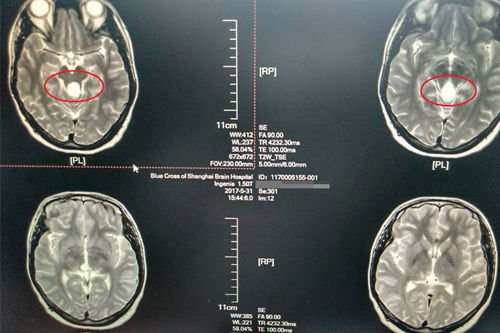

术前:核磁诊断松果体占位(图片中央白色区域)